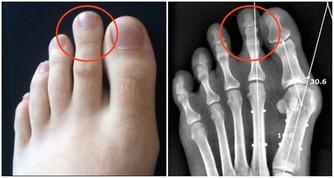

皺紋的暗示:臉頰是面部皮膚比較脆弱的地方,很容易看出血管方面的問題。如果右臉比左臉的皺紋深,大概是肝臟不好。面頰出現斜紋,查查有無高血壓。如果顴骨上出現鐮刀形皺紋,腳上可能有病。